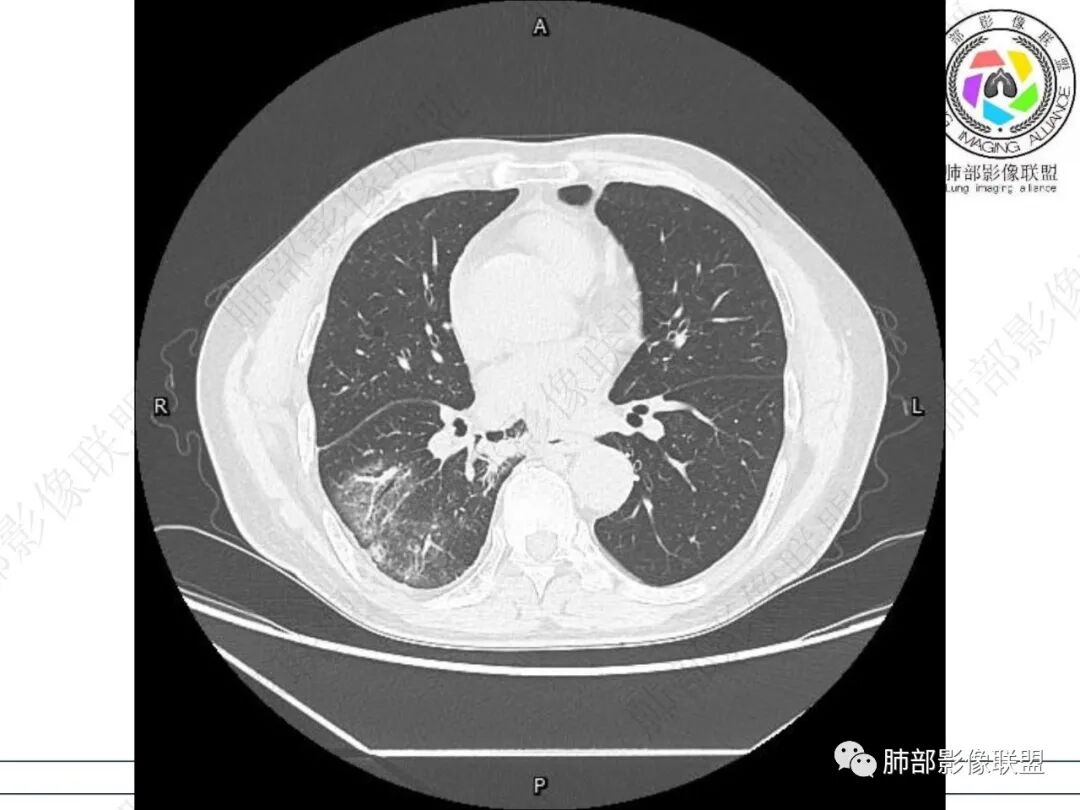

右肺下叶背段可见斑片状、条片状高密度影,支气管扩张,周围伴有磨玻璃影,边界欠清,纵隔窗:可见脊柱偏右侧可见斑片状影,与食管交界面欠清,食管形态不规则,考虑食管支气管瘘?食管异物穿孔?支气管异物?建议食管镜及支气管镜检查。

右肺下叶背段条片状实变影,内可见支气管走行,支气管有狭窄有扩张,周围可见磨玻璃影,隆突下团片影,内密度不均可见气体影,与周围结构界限不清。食管下段壁增厚,管腔狭窄,右肺下叶慢性炎、肺不张,考虑食道肿瘤所致气管食管瘘。

男性69岁,咳嗽,咳痰10多年。两肺下叶有支气管扩张的改变,右肺下叶背段的片状实变阴影,有支气管的扭曲样穿行,有病灶的收缩,以及沿着支气管的 播散病灶,肺门纵隔内支气管隆突的上下呈大片状的实变影,结构比较混乱,食管显示的不清楚,伴有多发的淋巴结增大。临床上主要提及呼吸道的症状,但是没有提及消化道的症状。另外还见到肝内有多发的低密度病灶,考虑囊肿。

右肺下叶沿肺叶肺段分布斑片、条片状影,以下叶背段为显,边缘模糊,内可见支气管走行,局部支气管管壁增厚,右侧胸腔少量积液。纵隔隆突下可见不均匀软组织密度影,与周围结构分界不清,内见气体密度影,与食管及相邻右肺支气管之间未显示通道。邻近食管下段壁明显不规则增厚,增强后食管管壁明显不均匀强化,可见线样强化的连续完整粘膜影。

对比患者3月份的CT图,原隆突下存在增大钙化淋巴结,现在出现气体影,且钙化显示不清,应想到淋巴结结核破溃成瘘可能性。